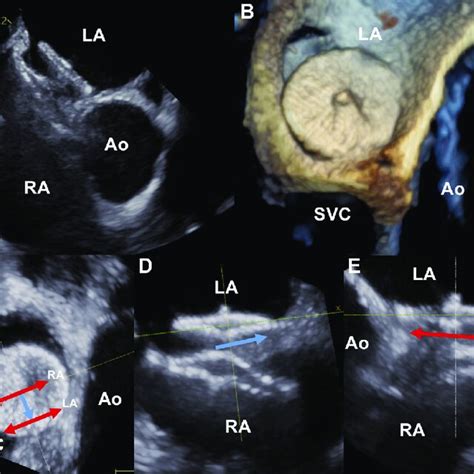

1470×1333

wjgnet.com

Novel way of patent foramen ovale detection and percutaneous closure b…